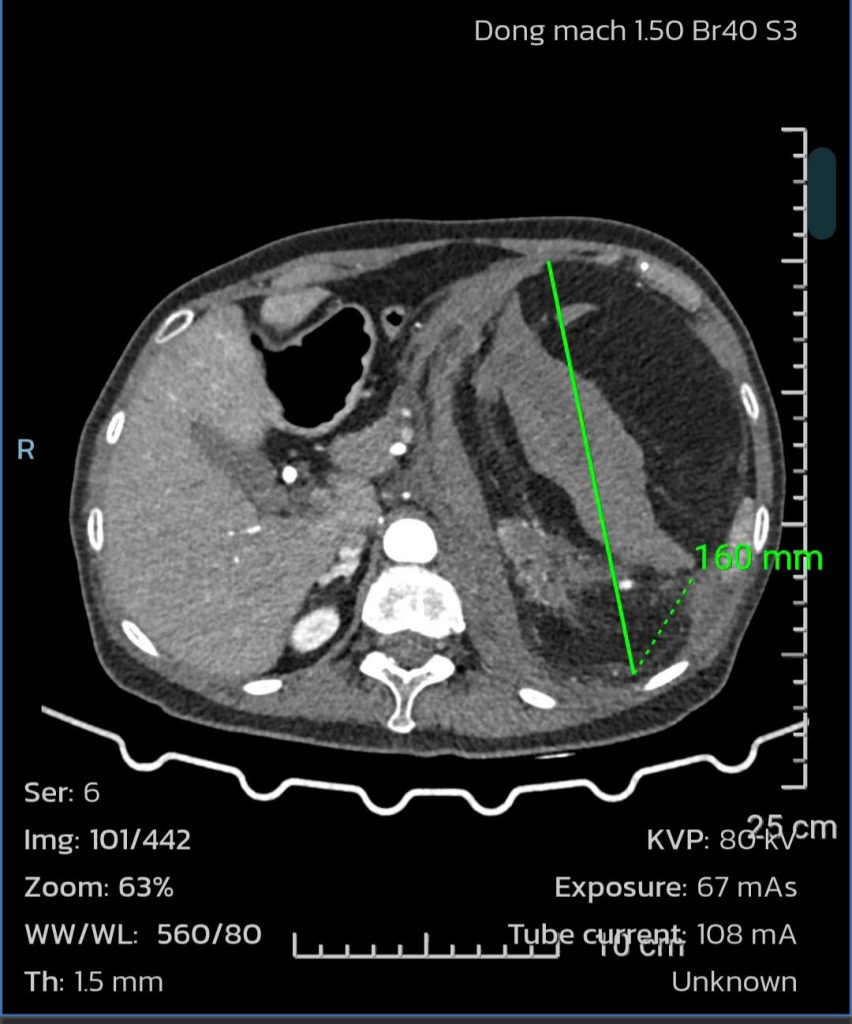

Vào một buổi sáng, bà bất ngờ lên cơn đau hông lưng bên trái dữ dội, cơ thể mệt mỏi, khó thở. Người nhà đưa bà đến một bệnh viện gần nhà thăm khám, kết quả chụp CT bụng phát hiện thận trái của bà có khối bướu ALM lớn, kích thước 16cm và có máu bên trong. Các bác sĩ nghi ngờ tình trạng xuất huyết sau phúc mạc do bướu vỡ – một biến chứng nguy hiểm có thể đe dọa tính mạng nếu không xử trí kịp thời.

Hình ảnh CT scan

Hình ảnh CT scan khối bướu thận gây xuất huyết